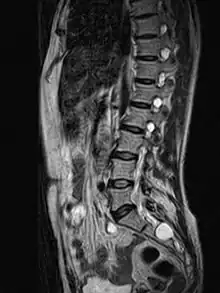

| MRI image showing a Tarlov cyst | |

Tarlov cysts, are type II innervated meningeal cysts, cerebrospinal-fluid-filled (CSF) sacs most frequently located in the spinal canal of the sacral region of the spinal cord (S1–S5) and much less often in the cervical, thoracic or lumbar spine. They can be distinguished from other meningeal cysts by their nerve-fiber-filled walls. Tarlov cysts are defined as cysts formed within the nerve-root sheath at the dorsal root ganglion.[2] The etiology of these cysts is not well understood; some current theories explaining this phenomenon have not yet been tested or challenged but include increased pressure in CSF, filling of congenital cysts with one-way valves, inflammation in response to trauma and disease. They are named for American neurosurgeon Isadore Tarlov, who described them in 1938.[3]

Tarlov cysts are relatively uncommon when compared to other neurological cysts. Initially, Isadore Tarlov believed them to be asymptomatic, however as his research progressed, Tarlov found them to be symptomatic in a number of patients. These cysts are often detected incidentally during MRI or CT scans for other medical conditions. They are also observed using magnetic resonance neurography with communicating subarachnoid cysts of the spinal meninges. Cysts with diameters of 1 cm or larger are more likely to be symptomatic; although cysts of any size may be symptomatic dependent on location and etiology. Some 40% of patients with symptomatic Tarlov cysts can associate a history of trauma or childbirth.[4] Current treatment options include CSF aspiration, fibrin-glue therapy, laminectomy with wrapping of the cyst, among other surgical treatment approaches. Interventional treatment of Tarlov cysts is the only means by which symptoms might permanently be resolved due to the fact that the cysts often refill after aspiration. Tarlov cysts often enlarge over time, especially if the sac has a check valve type opening. They are differentiated from other meningeal and arachnoid cysts because they are innervated and diagnosis can in cases be demonstrated with subarachnoid communication.

Both CT and MRI are good imaging procedures that allow the detection of extradural spinal masses such as Tarlov cysts. Magnetic resonance neurography is an emerging imaging technology based on MRI that highlights neurologic tissue. Often cysts are under reported and under diagnosed as radiologists and neurosurgeons have been traditionally taught to ignore these cysts. Patients frequently experience difficulty in diagnosis, however this is changing as Tarlov cysts have now been recognized by NORD as a rare disease.[16]

MRI

MRI, or Magnetic Resonance Imaging, is considered the imaging study of choice in identifying Tarlov cysts. MRI provides better resolution of tissue density, absence of bone interference, multiplanar capabilities, and is noninvasive. Plain films may show bony erosion of the spinal canal or of the sacral foramina. On MRI pictures, the signal is the same as the CSF one.

Tarlov cysts are most commonly located in the S1 to S4/S5 region of the spinal canal, but can be found along any region of the spine. They usually form on the extradural components of sacrococcygeal nerve roots at the junction of dorsal root ganglion and posterior nerve roots and arise between the endoneurium and perineurium.[10] Occasionally, these cysts are observed in the lumbar and thoracic spine.[7] However, these cysts most commonly arise at the S2 or S3 junction of the dorsal nerve root ganglion.[11][12] The cysts are often multiple, extending around the circumference of the nerve, and can enlarge over time to compress neighboring nerve roots, to cause bone erosion.[13] The cysts may be found anterior to the sacral area and have been known to extend into the abdominal cavity. These cysts, though rare, can be found to grow large - over 3–4 centimetres (1.2–1.6 in) in size, often causing severe abdominal pain from compression on the cyst itself as well as adjoining nerves.